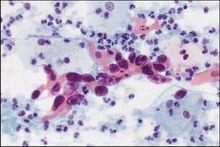

埃利希對白血球進行鑑別染色1878年獲博士學位後,埃利希受聘於柏林Charité醫院,先在著名的實驗病理學家、肝病學權威弗雷里希(FriedrichVonFrerichs)手下任助手,後提任為主治醫生。弗雷里希賞識埃利希的才幹,積極支持他的染色實驗研究,甚至取消了他的日常門診事務。從各方面看,這裡的實驗都非常簡陋,但幾乎他所有創造性的、重要的染色工作都是在這期間完成的。他的同事和清潔女傭對他經常在實驗桌上灑滿染料,頗多有微辭。一位同事就直截了當地說:“你一工作,桌上就留有染料痕跡。”他幾乎使用過當時發現的所有染料。1880年,他對白血球進行鑑別染色,創立了著名的三元酸染色法,並提出嗜酸性白血球、嗜鹼性白血球和嗜中性白血等術語。1882年,柯赫宣布發現結核桿菌。埃利希立即著手尋找一種新的、更靈敏的選擇性染色結核的方法。他利用這種微生物易和酸性物質結合的性質,創造了新方法,今天使用的各種方法都是在他的原始技術基礎上改進而成的。